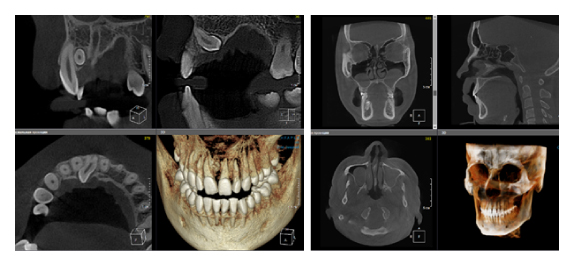

Когда мы отправляем пациента на проведение рентгенологического исследования, то подвергаем его определенному риску. Именно это нужно осознавать, так как в радиологии нет минимально безопасной дозы, поэтому любое назначение должно быть обоснованным. В связи с этим поле обзора является достаточно принципиальным параметром. Если вы врач-терапевт, занимающийся эндодонтией или ортопед, который решил оценить состояние зубов перед протезированием, то вы должны понимать, что проведение исследования с полем обзора 10x10 см будет гораздо информативнее нежели большие снимки (18x16 см и выше). В первую очередь это связано с размером вокселя, о нём я напишу чуть ниже, а второе это то, что вам придется увеличивать изображение по каждому корневому каналу, и от этого вы будете терять в качестве снимка (рис. 1). И ситуация наоборот, если вы ортодонт, то чтобы использовать весь диагностический потенциал, а также возможность загрузить данные для расчёта 3D цефалометрии, то вам нужны снимки, захватывающие весь лицевой отдел черепа. Таким образом, дентальный томограф должен обладать возможностью проведения исследований с разным FOV, обеспечивая нужды всех специалистов. Если ваша клиника базируется на терапевтическом, хирургическом и ортопедическом приёме, то на мой взгляд, можно рассмотреть дентальные томографы с полем обзора 10x10 см или 16x10 см. Последний больше актуален для тех, кто работает с ВНЧС, так как антропометрически в 16 см даже у брахицефалов сустав должен попадать. Если в клинике есть ортодонтическое направление, функциональная стоматология, ЛОР-практика или ЧЛХ, то, безусловно, вышепредставленные снимки не будут отражать всех данных, которые необходимы для диагностики и планирования лечения. Здесь лучше рассмотреть конусно-лучевые компьютерные томографы с зоной сканирования 18x16 или 20x20 см. Особо стоит отметить понятие «сшивки». Есть дентальные томографы, которые делают один цельный снимок размерами, которые описаны выше, а есть аппараты, которым нужно провести две экспозиции и сшить изображения вместе, чтобы получился необходимый объём исследования. Как правило, вторые томографы чуть дешевле, но всё зависит от того, насколько вам нужна максимальная точность исследования. Если при сшивке челюсти и зубы, как правило, совмещаются практически идеально, то на уровне позвоночного столба происходит наслоение тканей и от него уже не избавиться (рис. 2). Второй отрицательный момент – это износ оборудования, логично, что он будет быстрее, так что экономия средств — это ещё спорный вопрос.

Рис. 1. Представлены два исследования (10x10 см и 20x20 см). На обоих изображениях хорошо видна канально-корневая система зубов, но, если масштабировать второе исследование, то качество неминуемо снизится, как и диагностическая эндодонтическая эффективность.

Рис. 2. Левый снимок представлен исследованием 20x20 см единым изображением. Стрелками показаны чёткость канально-корневой системы зуба, а также позвоночника. Правый снимок представлен исследованием 16x15 см с функцией сшивки. Стрелками обозначены чёткость зуба, но двойной контур позвоночника.